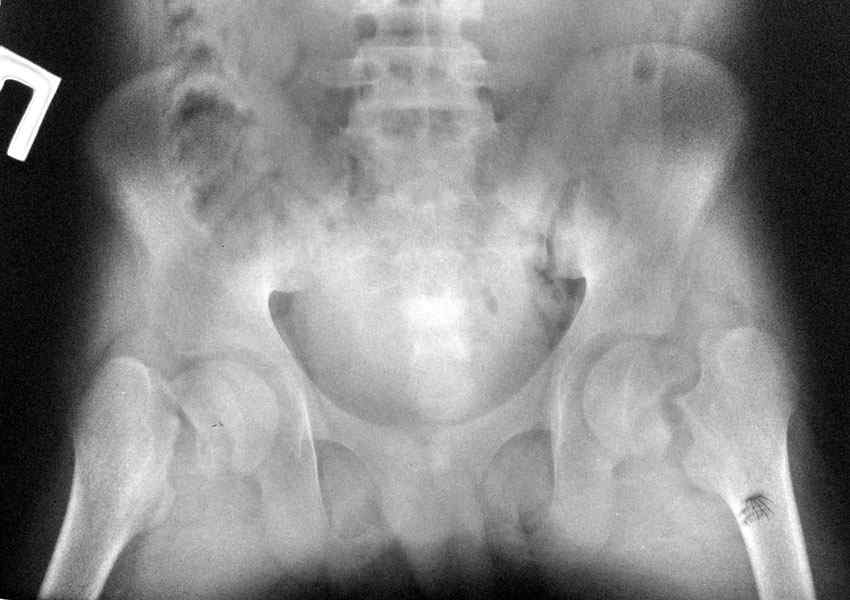

ренальная остеодистрофия и двусторонний перелом шеек бёдер

Больной 14 лет с врождённой аномалией развия почек. Уретрогидронефроз справа. Вторично сморщенная почка.ХПН терминальная стадия. На фоне гемодиализа двусторонний трансцервикальный перелом бёдер.

В течении 6 мес. по настоящее время скелетное вылежение по м.ж. в областном городе.

В настоящее время проводится терапия в составе: гемодиализ 3,5 часа 3 раза в неделю, Кальций Д3 никомед, Альфа Д3 0,25 мкг ежедневно,+ терапия вторичной гипертензии.